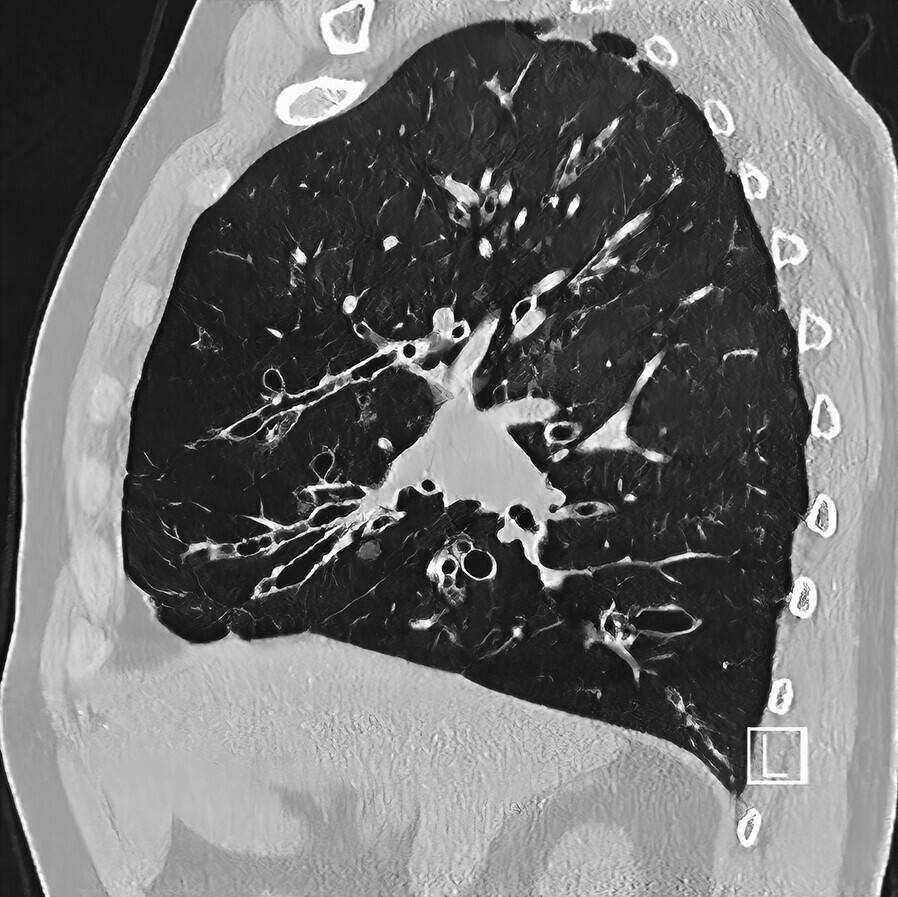

- Diagnose wird im CT gestellt, hierzu ist ein HRCT wichtig (Abb. 75.3)

- Typischer Befund: irreguläre bis monströse Bronchuserweiterung im Bereich der 6.-8. (zylindrische) oder 5.-7. (sakkuläre) Bronchusgeneration, verdickte Bronchuswand, peribronchiale Infiltration, Flüssigkeitsfüllung in den Mittel- und Unterfeldern.

- Tram-Track-Zeichen: longitudinaler Anschnitt eines verbreiterten Atemwegs ohne Verschmälerung.

- Atemwege zeigen einen größeren Durchmesser als die begleitende Arterie (Siegelringzeichen).

- Wertung: direkte Darstellung mit topografischer Zuordnung, gleichzeitige Darstellung der Folgezustände (Parenchymdestruktion, Aspergillom).

- Die Verteilung der Veränderungen im CT ergibt Hinweise auf die Ätiologie: Oberfeld, CF, TBC, Silikose, Sarkoidose; Mittelfeld, PCD, Aspirationen, Mittellappen-Syndrom, NTM; Unterfeld, PCD, Aspirationen, CTD, AATD.

- Füllung mit Schleim (Mucus plugging).

- Die Inspirationslage bei der Durchführung des CT beeinflusst die Darstellung, insbesondere die Weite der Atemwege.

Abb. 75.3 Bronchiektasen in der hochaufgelösten CT-Aufnahme (HRCT).

(Quelle: Klinik für Diagnostische und Interventionelle Radiologie, UKS)